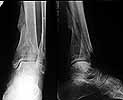

A female 56 y.o. 6 weeks ago sustained a fracture of the distal tibia/fibula. At the initial hospital a plaster cast was applied. Now she was referred to our unit. At the moment there is no pain, no obvious mobility. Images and CT attached.

What is the best option here? Mobilize the fracture, perform open reduction and internal or external fixation? Or just to cut the anterior spike over the talar neck? THX in advance.